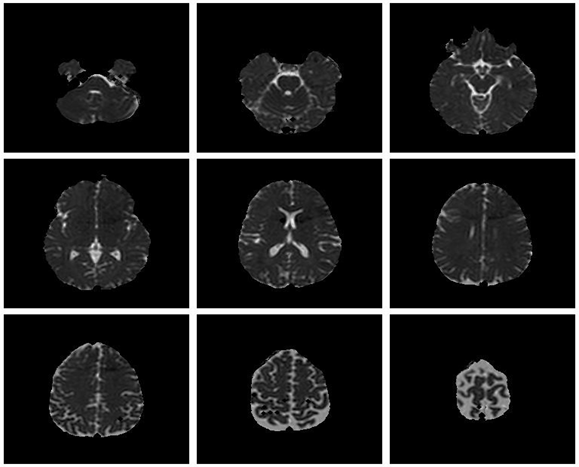

Save Image 3x3 (Original Image / Clustered Image): Save 9 slices of the scan to a PNG file (Figure 5). The name of the file will be the detailed title of the image 3x3.